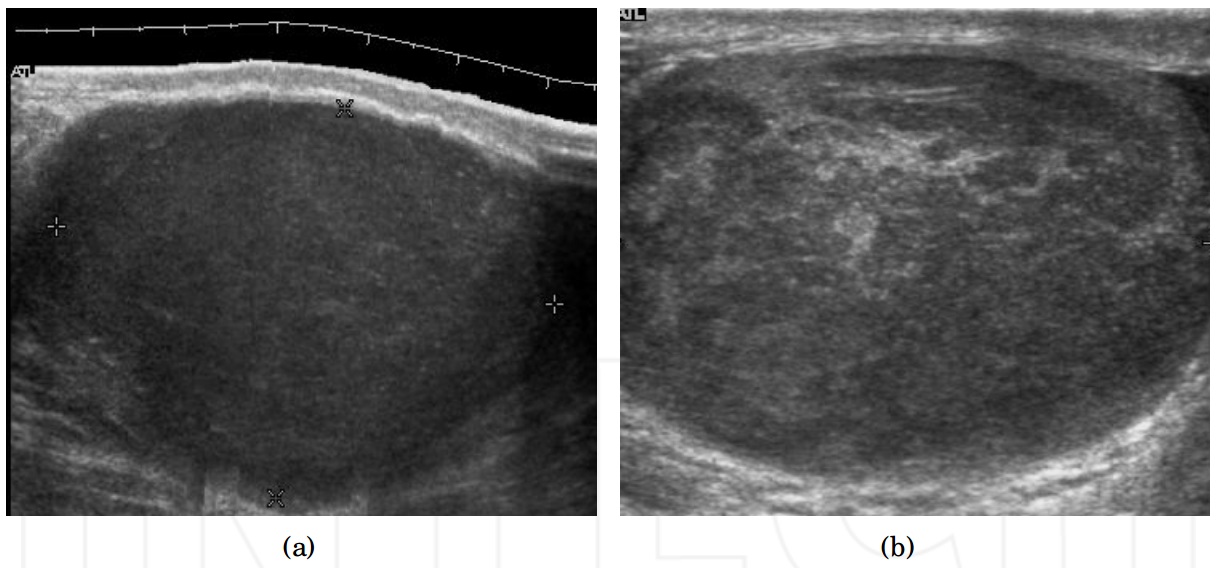

Ormai è risaputo come funziona un’ecografia, esame durante il quale viene applicato un gel sulla superficie interessata e successivamente tramite il passaggio di una sonda vengono emessi ultrasuoni che permettono di creare un immagine dell’interno del nostro corpo. Un esame facile e indolore svolto in circa 15 minuti tipicamente prescritto in presenza di dolori, infertilità, traumi, palpazione di noduli o come controllo. Permette di individuare diverse patologie molto diffuse tra gli uomini, tra cui varicocele, idrocele, torsione testicolare, epididimite, orchite, cisti, ematomi e tumori. Per quanto non venga usato come test di screening ma come esame di approfondimento, può essere utile fare un controllino una volta ogni tanto per prevenire eventuali problemi, in quanto come abbiamo detto, troppo spesso gli uomini non hanno un buon rapporto con il medico, soprattutto quando riguarda certe zone. Per chiunque voglia cambiare questa regola distorta e lottare per la propria salute, consigliamo di prenotare una Ecografia testicolare a San Lazzaro vicino Bologna presso il poliambulatorio San Lazzaro dove esperti si prenderanno cura di qualsiasi problema.